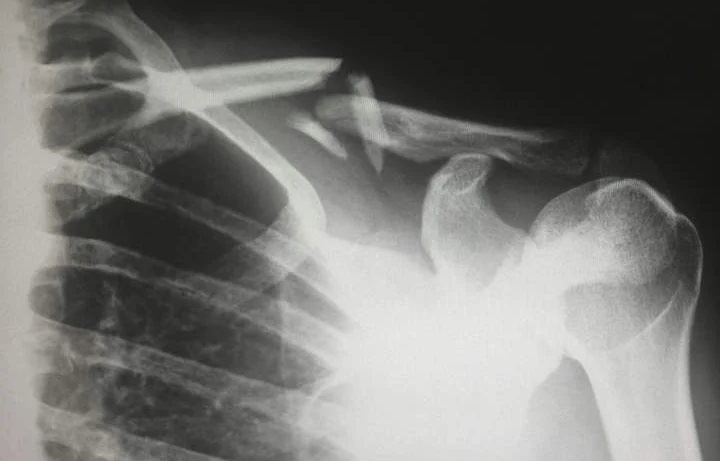

Một phụ nữ bị gãy xương do nghi ngờ thiếu vitamin D.